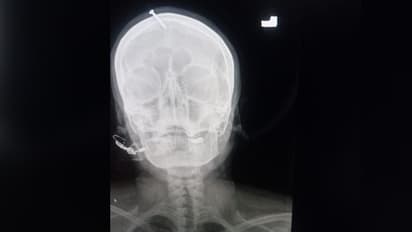

പാക്കിസ്താനില് ആണ്കുഞ്ഞിനെ കിട്ടുമെന്ന് പറഞ്ഞ് ഗര്ഭിണിയുടെ തലയോട്ടിയില് വ്യാജസിദ്ധന് ആണി അടിച്ചിറക്കി. തലയില് ആണി കേറിയതിനെ തുടര്ന്ന് രക്തം വാര്ന്നതിനെ തുടര്ന്ന് ഈ സ്ത്രീയെ ആശുപത്രിയില് പ്രവേശിപ്പിച്ചു. അടിയന്തിര ശസ്ത്രക്രിയയിലൂടെ ഇവരുടെ തലയിലെ ആണി പിഴുതെടുത്തതായി ഡോക്ടര്മാര് അറിയിച്ചു. ആണി തറഞ്ഞുകേറിയ തലച്ചോറിന്റെ എക്സ്റേ ഇമേജ് സോഷ്യല് മീഡിയയില് വൈറലായതിനെ തുടര്ന്ന് പാക് പൊലീസ് വ്യാജസിദ്ധനു വേണ്ടി വ്യാപക അന്വേഷണം ആരംഭിച്ചു.

പെഷവാറിലെ പ്രമുഖ ആശുപത്രിയിലാണ് കഴിഞ്ഞ ദിവസങ്ങളിലൊന്നില് ഗുരുതരമായ അവസ്ഥയില് സ്ത്രീയെ കൊണ്ടുവന്നത്. ഇവര് ഗര്ഭിണിയായിരുന്നു. തലയില്നിന്നും ചോരവാര്ന്ന നിലയില് അബോധാവസ്ഥയിലാണ് ഇവരെ കൊണ്ടുവന്നത് എന്നു ഡോക്ടര്മാര് പറഞ്ഞു. തുടര്ന്ന് എക്സ് റേ എടുത്തപ്പോഴാണ് തലച്ചോറില് ആണി തുളച്ചു കയറിയതായി മനസ്സിലായത്. ഇതിനു ശേഷം, ഡോക്ടര്മാര് അടിയന്തിര ശസ്ത്രക്രിയ നടത്തി. ഇവരുടെ നില സുരക്ഷിതമായതിനെ തുടര്ന്ന് വീട്ടിലേക്ക് പറഞ്ഞയച്ചു.

സ്ത്രീയുടെ തലച്ചോറിന്റെ എക്സ്റേ റിപ്പോര്ട്ട് സോഷ്യല് മീഡിയയില് പ്രചരിച്ചതോടെയാണ് സംഭവം പുറത്തറിഞ്ഞത്. തുടര്ന്ന്, പൊലീസ് സ്വമേധയാ കേസില് ഇടപെട്ടു. ഇവര് നടത്തിയ അന്വേഷണത്തിലാണ്, നടന്ന സംഭവത്തെക്കുറിച്ച് യുവതി മൊഴി നല്കിയത്. തുടര്ന്ന് പൊലീസ് സംഭവം ഗൗരവമായി എടുക്കുകയും പ്രത്യേക അന്വേഷണ സംഘം രൂപവല്കരിക്കുകയും ചെയ്തു.